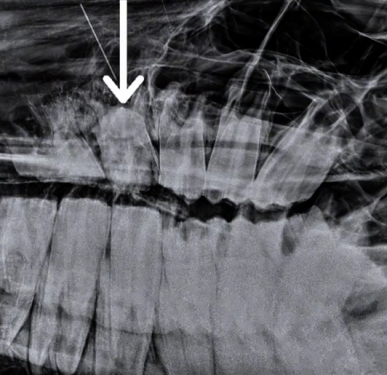

НА ВИДЕО: На осмотре у данного пони отмечалось появление свищевого хода в области верхней челюсти. Был выявлен патологический зуб с частичной фрагментацией коронки, изменение положения относительно зубного ряда в левую сторону. Это вызывало у пациента дискомфорт и болезненные ощущения. Было решено удалить этот «беспокоящий» зуб.

Рентгенологическое обследование также подтвердило наличие апикальной инфекции и скученность зубного ряда. Кроме того, по результатам рентгена и стоматологического осмотра на данном зубном ряду обнаружена гиподонтия, что также указывает на врожденую аномалию.